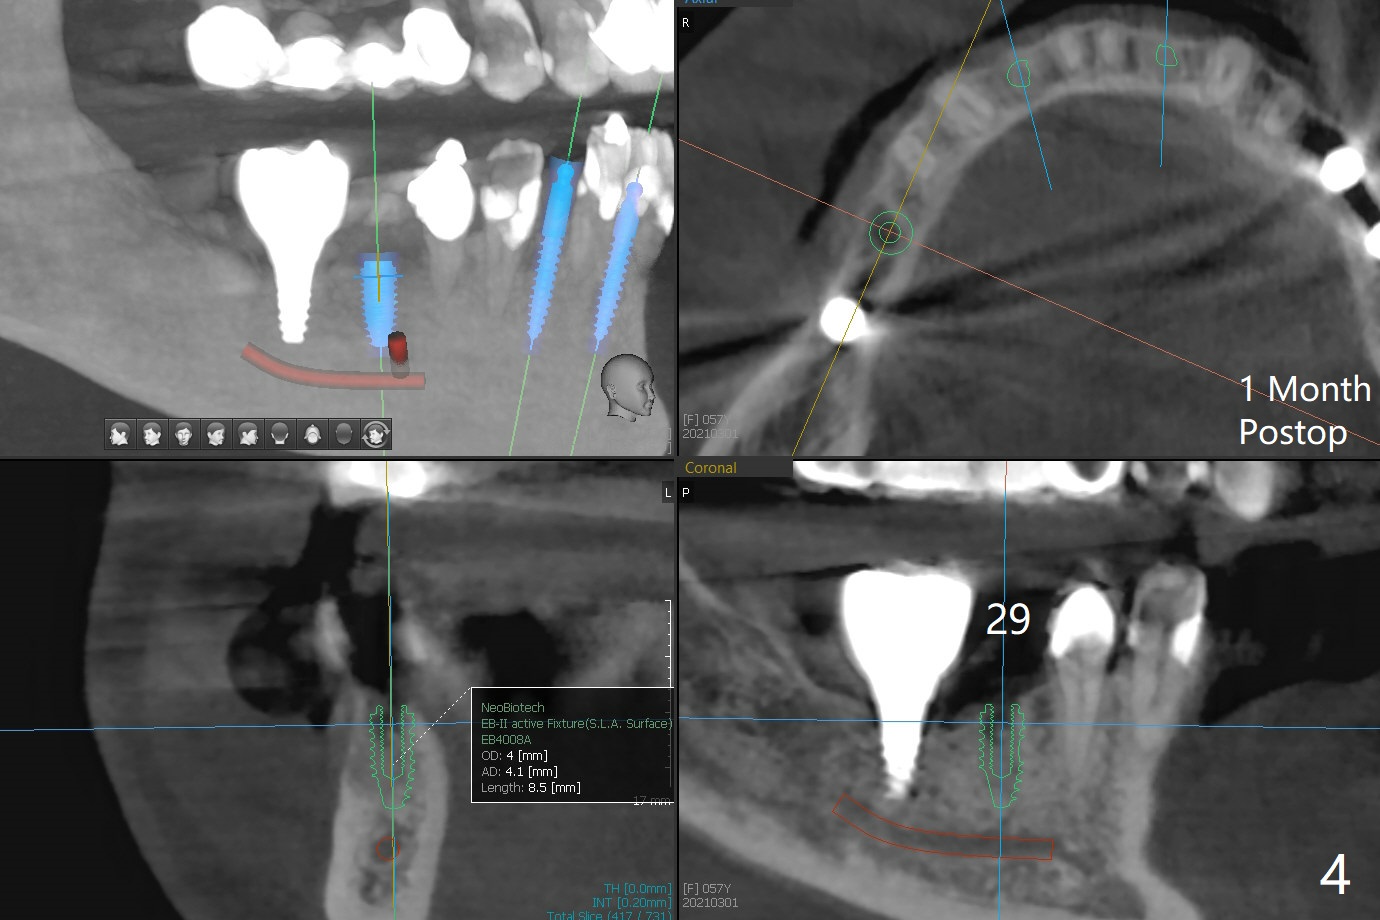

57岁女,口干症,前一个月(23,29号牙),三个月(26号牙)拔除植骨,可能需要再等一个月(出差)才能手术,会不会太早植牙?骨质还不够

Xin Wei, DDS, PhD, MS 1st edition 03/01/2021, last revision 04/01/2021